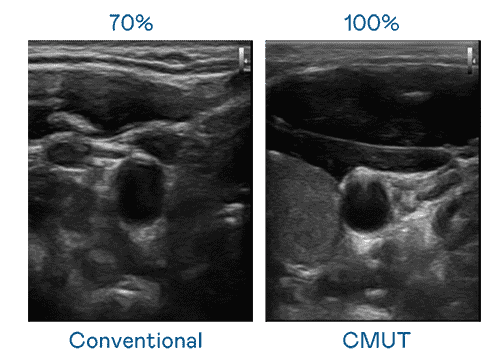

CMUT 技术是一种用电容式微机电元件来产生超音波讯号的技术。。与传统 PZT 压电式技术相比,,CMUT 频宽增加 30%,,更宽频的超音波讯号让影像解析度大幅提升,,,,是实现高影像品质医疗超音波扫描、、、、促进精准医疗发展的关键技术。。

大频宽带来超清晰影像

超音波影像的解析度高低,,,,首先取决于探头能发出的讯号频宽。。OBPay CMUT 可提供高清晰的超音波讯号,,提供高频宽、、、高灵敏度、、影像纹理细节更高的超音波影像,,,协助医护人员缩短影像判读时间及利用精准的医疗影像进行诊断。。